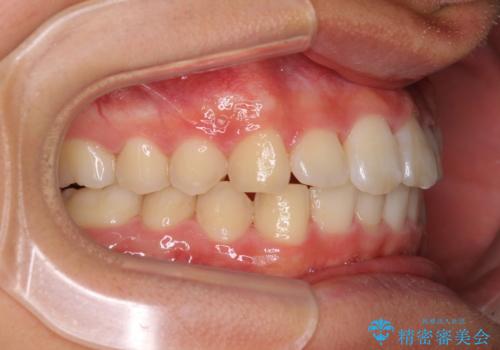

深い咬み合わせとデコボコ ワイヤー矯正で短期治療

インビザラインでの治療も可能でしたが、深い咬み合わせと奥歯の咬み合わせを改善するにあたり、ワイヤー矯正の方が治療期間を短縮できると判断し、ワイヤー矯正をお勧めしました。

結果として、1年かからずに奥歯の咬み合わせを改善することができました。